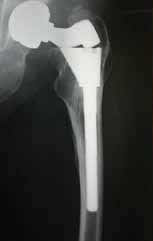

From 1986 to May 2012 a total of 1,114 modular stems have been implanted for primary THA by the senior author.

- S-Rom® Stem (DePuy) = 537

- Apex Modular™ Stem (Omnilife) = 116

- Apex K2 Modular™ Stem (Omnilife) = 341

- Apex ARC™ Stem (Omnilife) = 120

All stems implanted by the same surgeon utilizing the posterior surgical approach. All the femoral stems are manufactured from titanium alloy (ASTM F136).

S-Rom

- Modular junction failures = 0

- Dislocations = 6 total (3 closed reductions, 3 open constrained sockets)

Stem Revisions

- 4 total (0 for aseptic loosening, 4 late sepsis)

Painful Hip

- 5 pts: Required on-lay grafting for signifi cant progressive end of stem pain.

Painful S-Rom stem required on-lay strut grafting

Apex Modular & Apex K2 Stem

- Aseptic loosening = 0

- Stem Revisions = 0

The Apex ARC™ Neck Sparing Stem

- Stem revisions = 2

In over 1,114 primary cementless total hip arthroplasties performed by the same surgeon in two community hospitals over 26 years, there has never been a related modular junction failure. There have been no signs of pseudo tumors, surface corrosion, metallosis, etc.